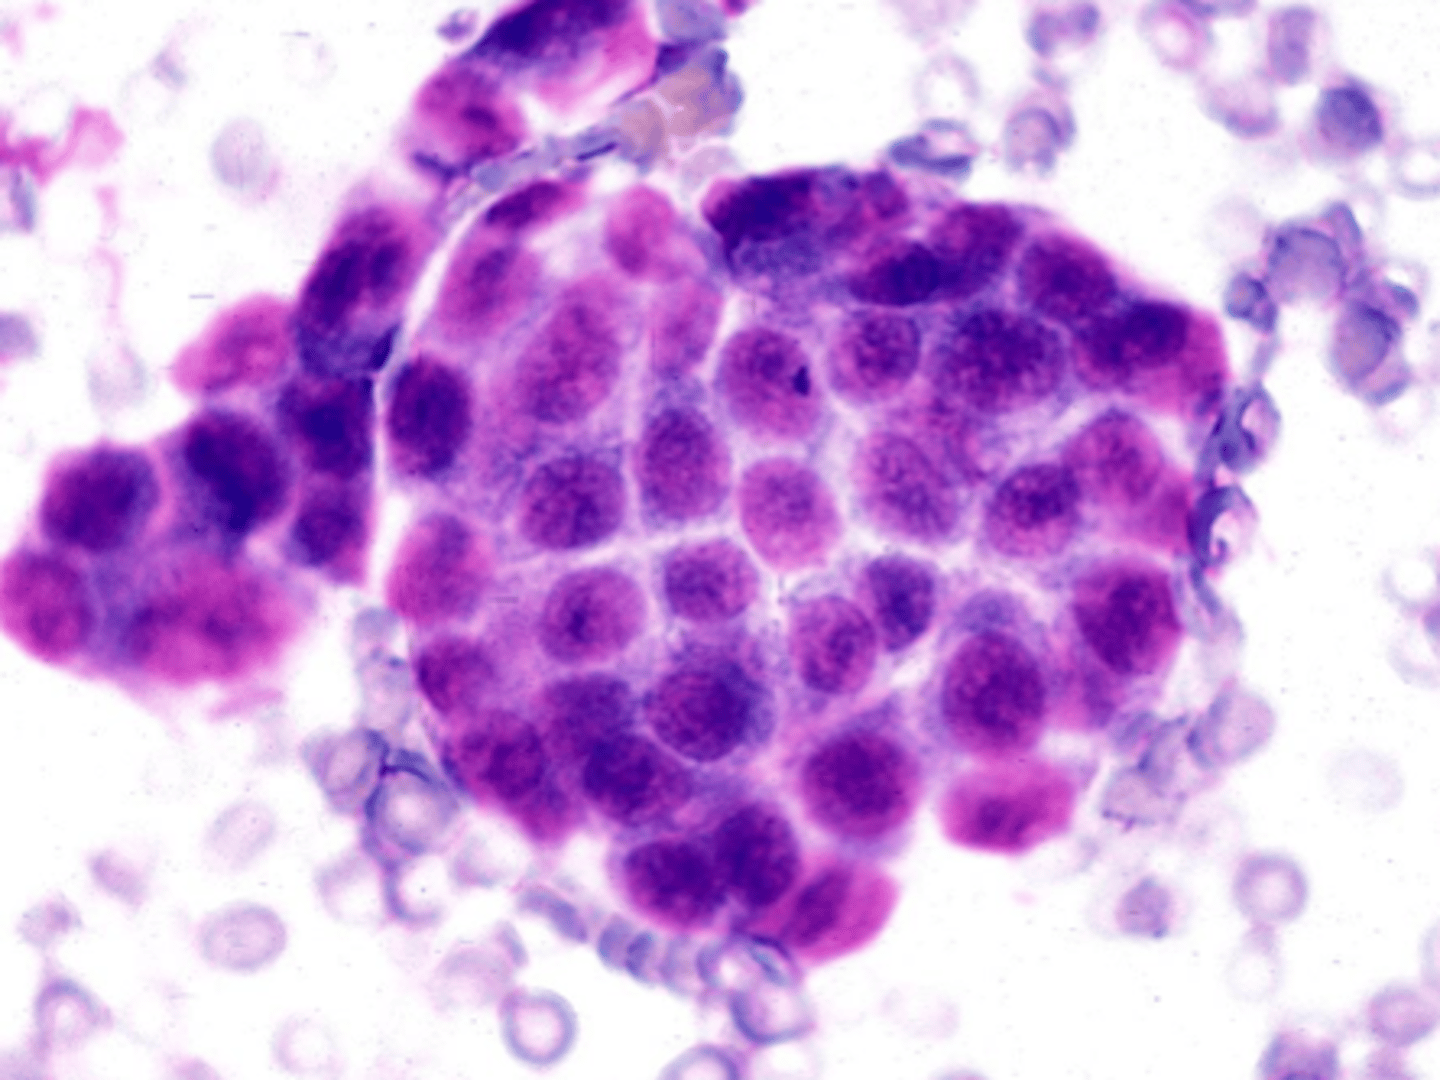

Identify the type of round cell neoplasia?

Lymphoma